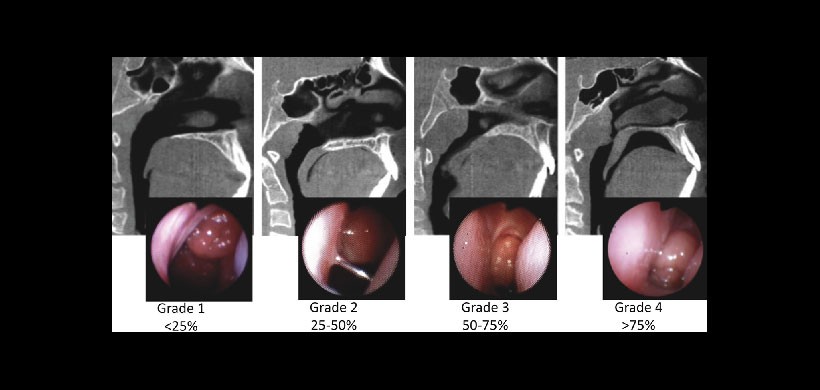

| Grado 1 (sano) | No se evidencia aumento del volumen del tejido adenoideo, la amígdala puede estar ocupando y generando una obstrucción considerada normal de 0 – 25% |

| Grado 2 (leve) | Es la condición en la cual el tejido adenoideo tiene un volumen que compromete al torus tubarius. Existe una obstrucción a nivel de la coanas de 25 – 50% |

| Grado 3 (moderado) | El tejido adenoideo tiene un mayor volumen, compromete al torus tubarius y a la mucosa del hueso vómer. Existe una obstrucción a nivel de las coanas de 50 a 75 % y solo es visible la parte inferior. |

| Grado 4 (severo) | Es la condición en el que existe una obstrucción prácticamente completa, llega a tener contacto con el paladar blando. Existe una obstrucción a nivel de las coanas de más del 75 % |

Cuadro 1: a) Clasificación del grado de hipertrofia denoidea.

Figura 1: Clasificación de la severidad de la hipertrofia adenoidea de acuerdo a las estructuras anatómicas comprometidas Parikh SR, et al.

Figura 2: Clasificación de la severidad de la hipertrofia adenoidea validada tomográficamente por Major MP, et al.